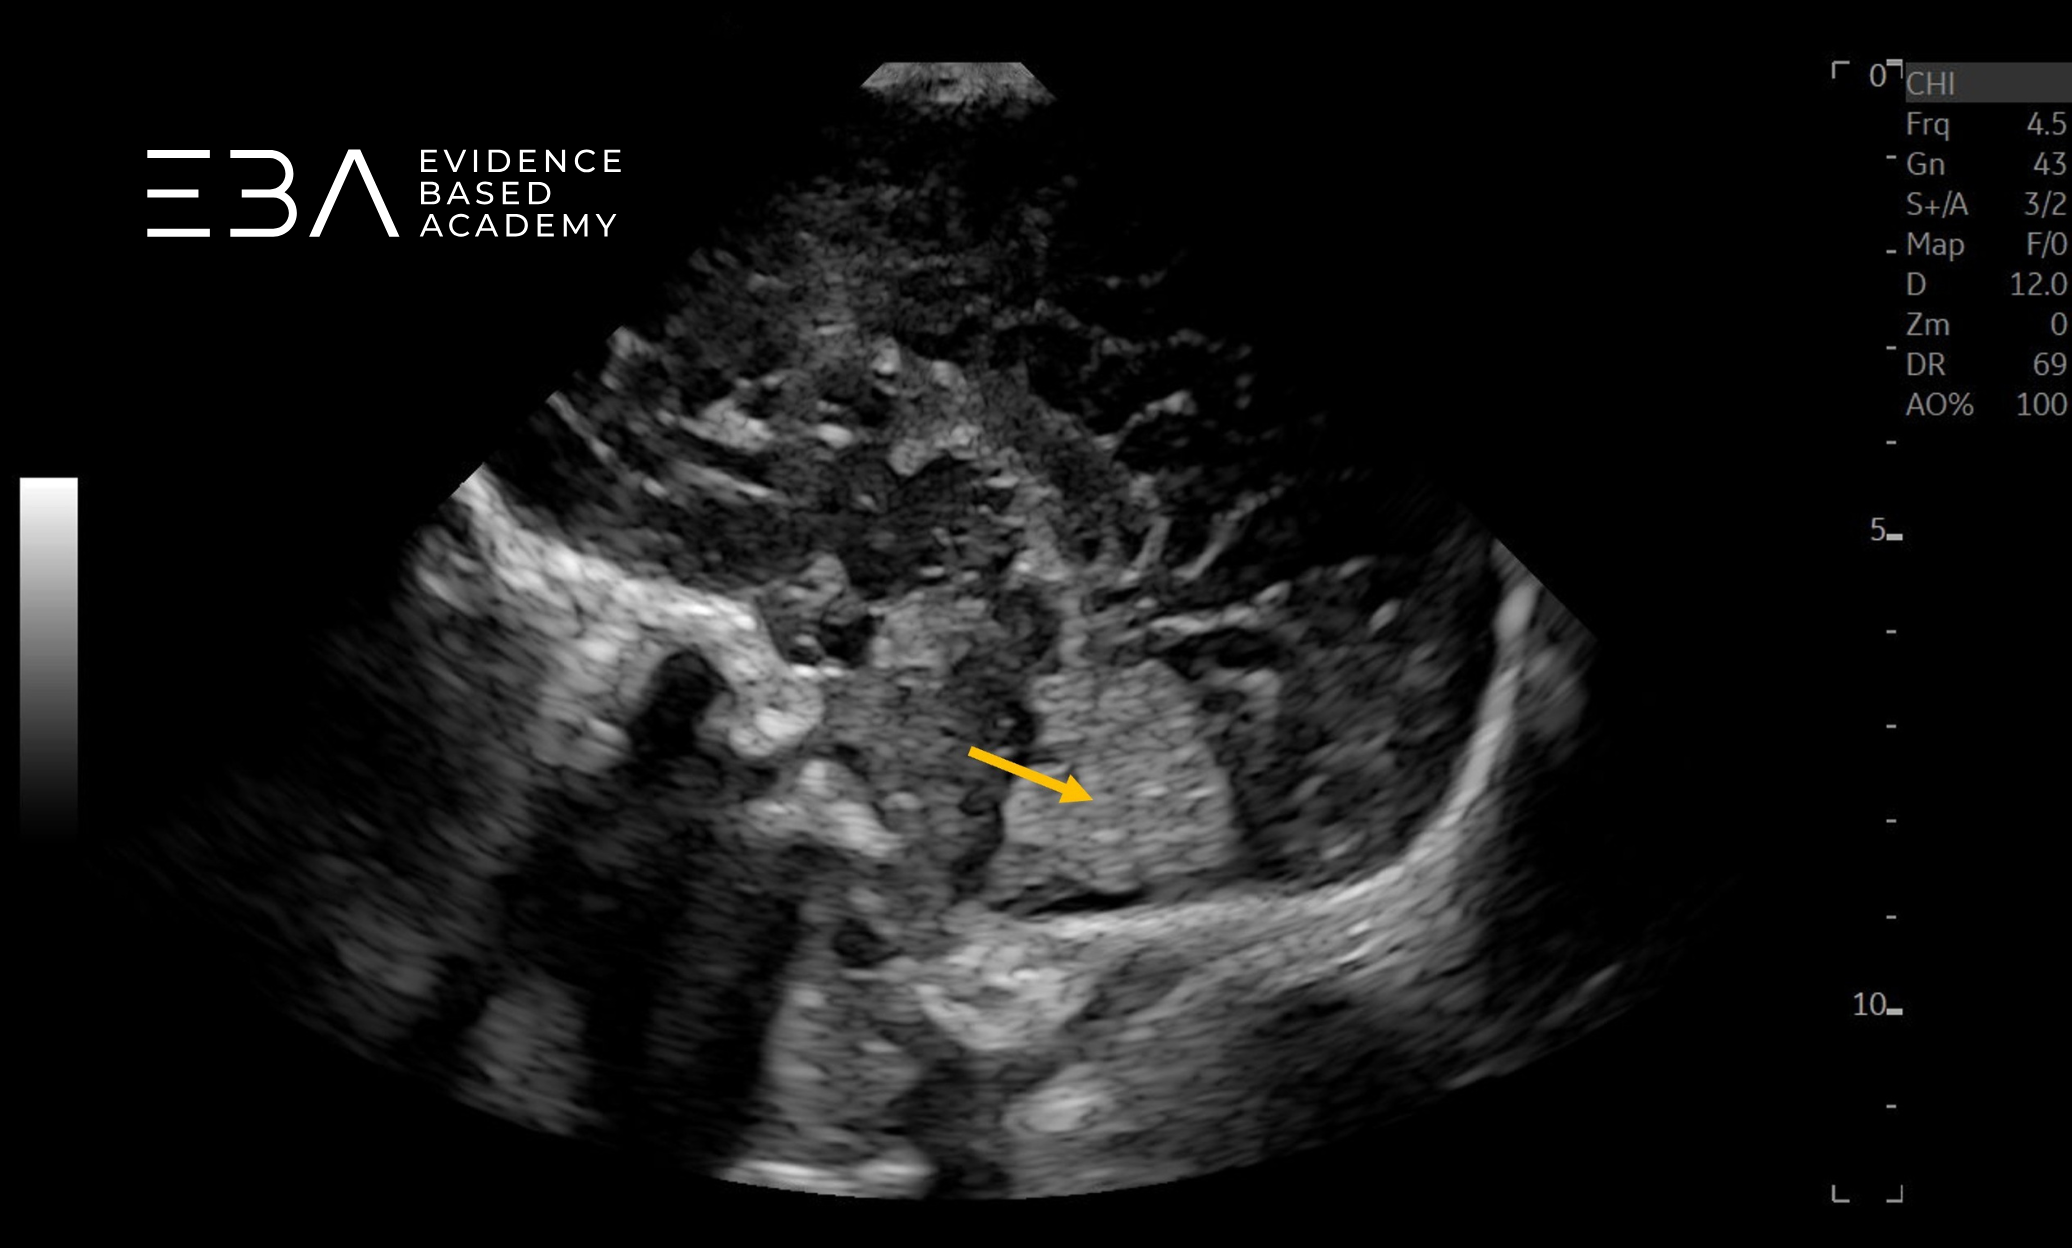

zdj. 1

Głowica mikrokonweksowa. Brak symetrii, wynikającej z nieco skośnego przyłożenia głowicy utrudnia ocenę. Strzałką zaznaczono prawy splot naczyniówkowy.